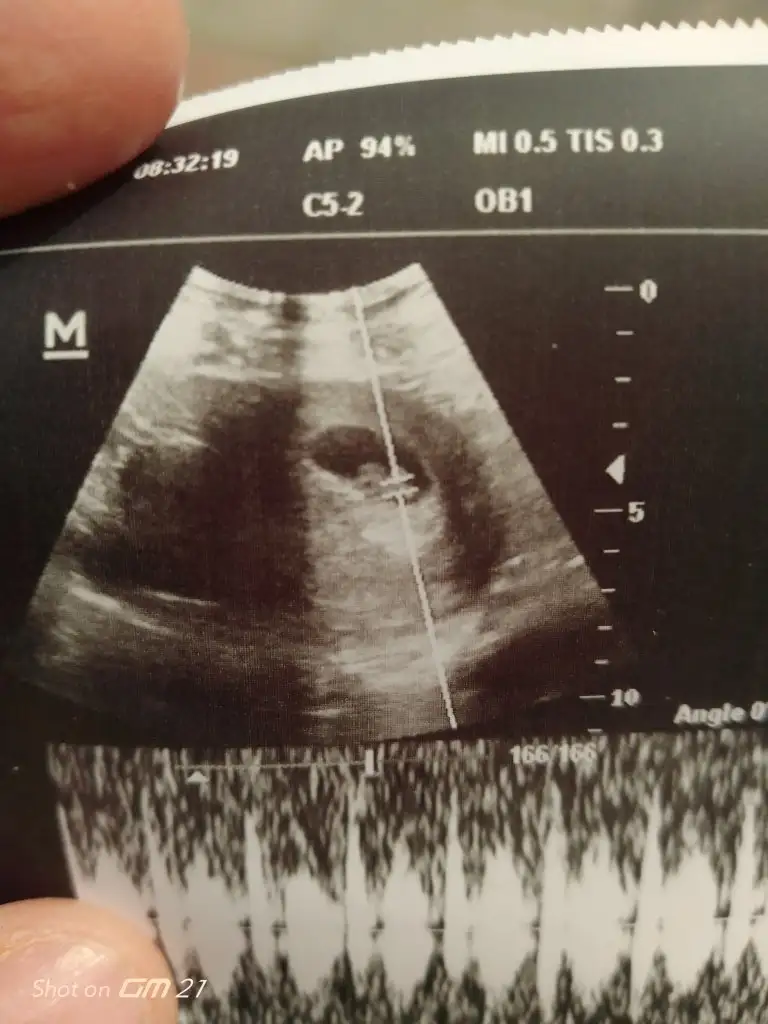

8+6 haftalık ama ultrason da 8+1 ile uyumlu doktor hiç bir şey söylemedi hatta oruç tutabilir miyim dedim dalga geçer gibi sence dedi daha da bişey demedi bizim aileye tek yumurta ikizleri var öle bi durum mevcut mu dedim cevap alamadım ilçede tek doktor ultrasyon görüntüsüne göre bolemi oluyo kalp atışı duyduk